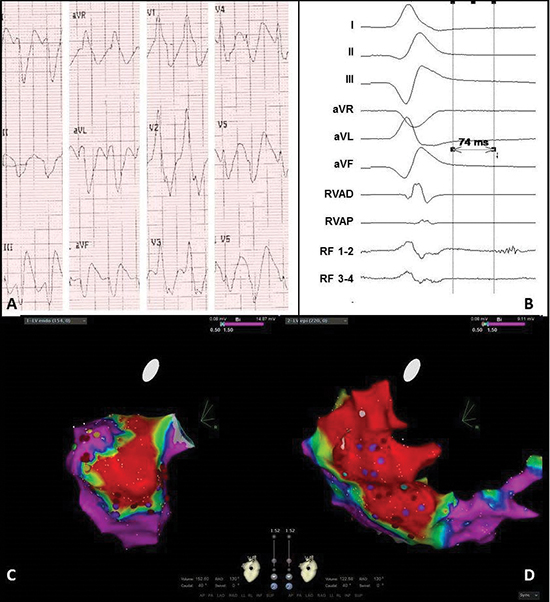

Figure 4 Electrocardiogram and electro-anatomical maps of case 2

A. Twelve-lead electrocardiogram showing a ventricular tachycardia (150bpm) with right bundle branch block morphology, right axis and normal R-wave transition suggesting a lateral-basal origin in the left ventricle.

Pseudo delta wave and wide QRS suggest epicardial origin.

B. Recording obtained in sinus rhythm during the procedure showing local abnormal ventricular activation. RVAD/P = right ventricular apex distal/proximal, RF = radiofrequency.

C. Inferior view of the bipolar endocardial voltage map showing low voltages inferior/inferoposterior (area 5/6). Red dots = RF applications, purple dots = late potentials.

D. RAO view of the bipolar epicardial voltage map showing low voltage area practically consistent with the endocardial map, though more extensive at the lateral wall (area 7/8). Red dots = RF applications, purple dots = late potentials.